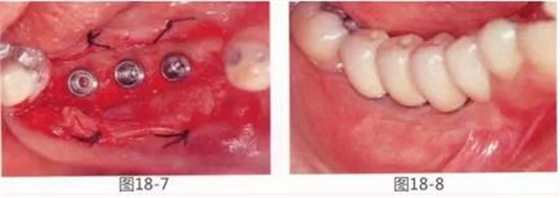

圖18-7 將種植體埋入后的狀態(tài)。

圖18-8 術(shù)后1年6個月。配裝上部結(jié)構(gòu)時的狀態(tài)。